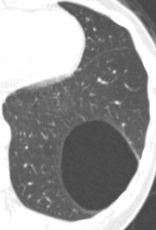

女性,50岁,2018年,体检巨大肺囊肿。2021年复查,囊肿缩小,后壁有10mm实性结节。2020年有高原旅行,剧烈疼痛病史。

2021年CT

最终诊断:肉芽肿